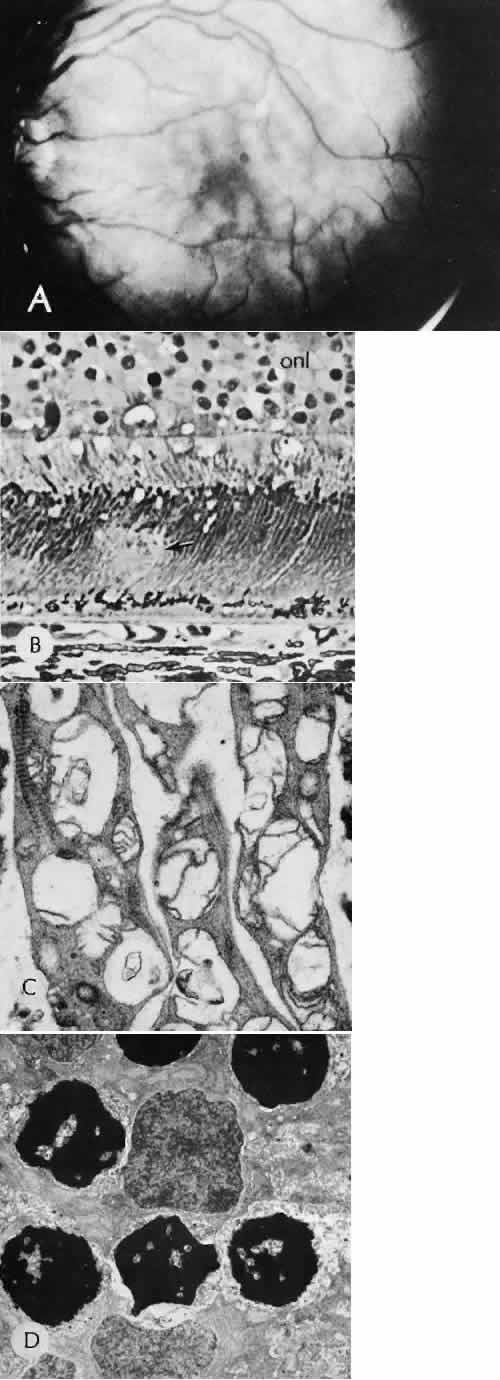

RETINAL HEALING

Wound healing of the neurosensory retina follows the principles of wound healing. There is an initial removal of all necrotic tissue by phagocytosis followed by proliferation of cells to form a chorioretinal bond. The healing, however, is modified in most instances by the lack of participation by the blood vessels.43–45 Astrocytes from the neurosensory retinaproliferate from the peripheral viable tissue into the wound and downward into the area of the subretinal space (Fig. 12). Retinal pigment epithelial cells from the peripheral viable tissue undergo fibrous metaplasia and proliferate upward into the area of the subretinal space. When the two proliferating cell types unite, a tight chorioretinal bond is formed. Increased retinal adhesiveness has been estimated to be 140% of the normal degree of adhesiveness 2 weeks after photocoagulation.46 Retinal holes may heal spontaneously if supported by an intact vitreous base or if located adjacent to the retinal pigment epithelium (Fig. 13).47,48 For the retinal pigment epithelium to differentiate, it must be in contact with overlying retinal pigment epithelium.49 Choriocapillaris repair from a photocoagulation wound of the retina appears to proceed in a manner similar to that of repair of capillary thrombosis in other tissues.50 The vascular repair process may not reproduce the lobular architecture of the native choriocapillaris.51 The choriocapillaris may regenerate in areas of restored retinal pigment epithelium.52 Proliferative vitreoretinopathy is an expression of abnormal retinal wound healing.53

Fig. 12. Light micrograph of an area over a retinal buckling element for retinal reattachment. Cryotherapy has been applied in the area, causing atrophy of the neurosensory elements of the retina. There is an intimate association of the remaining glial elements of the retina (R) with proliferated retinal pigment epithelial cells in the plane of the former subretinal space (arrow). The adhesion prevents intraretinal separation in this area. (Periodic acid-Schiff stain; × 100.)

Fig. 13. Retinal healing by proliferation of glial cells. In the presence of an intact vitreoretinal interface acting as a scaffolding, retinal glial cells are able to proliferate and seal small retinal holes. The arrow indicates artifactually detached vitreoretinal interface.